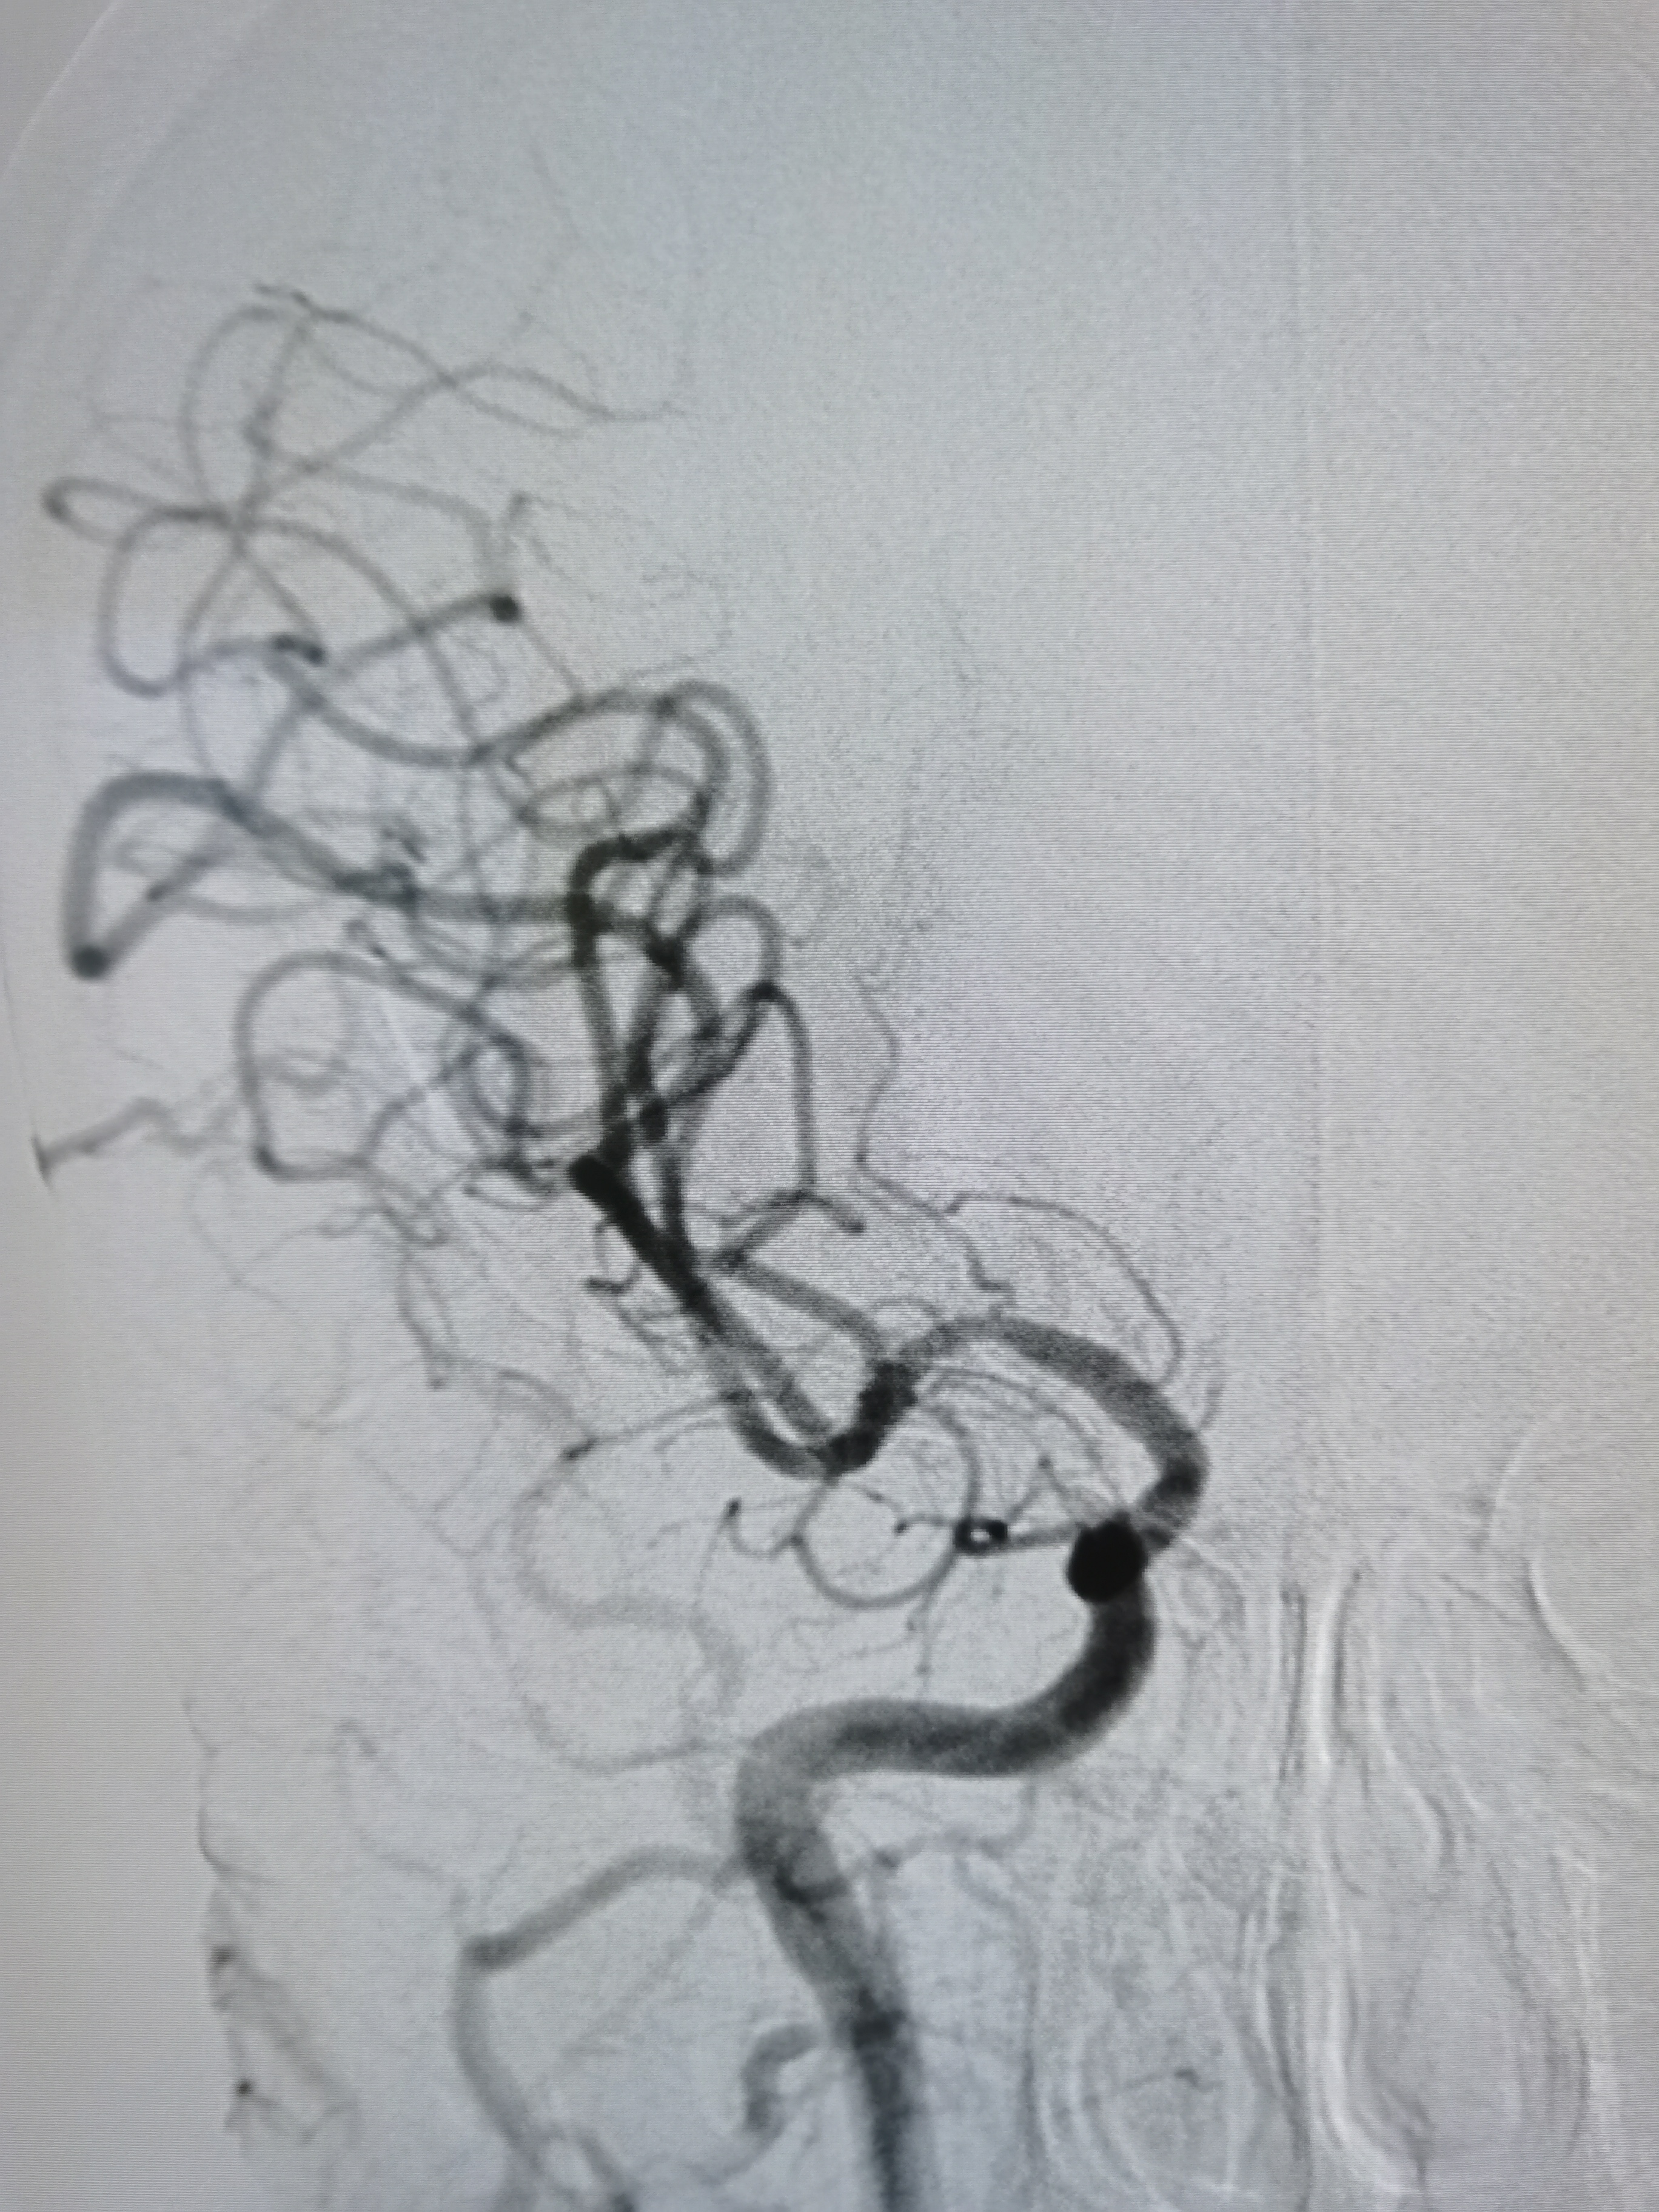

颅内段显影可。

右侧孤立大脑中动脉,M1轻度狭窄。

颅内血供良好。